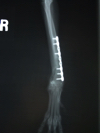

これまた小型犬の橈尺骨の骨折です。関節に近い場所なので固定が難しいです。

超小型犬の前足(橈尺骨)の骨折です。

当院ではロッキングプレートシステムを2kg以下のワンちゃんには1.2mm、

そこから体重や骨の太さに応じて1.5mm、2.0mm、2.4mm、さらには3.5mmのシステムで対応しています。